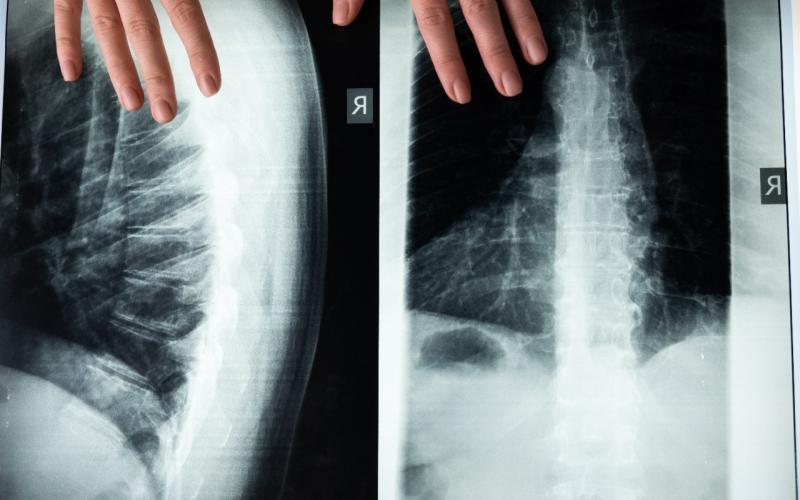

La médula espinal es una estructura cilíndrica aplanada de tejido nervioso que se encuentra en el conducto raquídeo de la columna vertebral, es la encargada de transmitir impulsos nerviosos a los nervios raquídeos que van desde el encéfalo a todo el cuerpo.

La médula espinal se extiende desde la base del cráneo hasta un poco por debajo de la mitad de la espalda y funciona a través de 2 formas: una es enviando las sensaciones hacia el cerebro para evaluar los movimientos de regreso hacia el resto del cuerpo (cuello, tronco y extremidades).